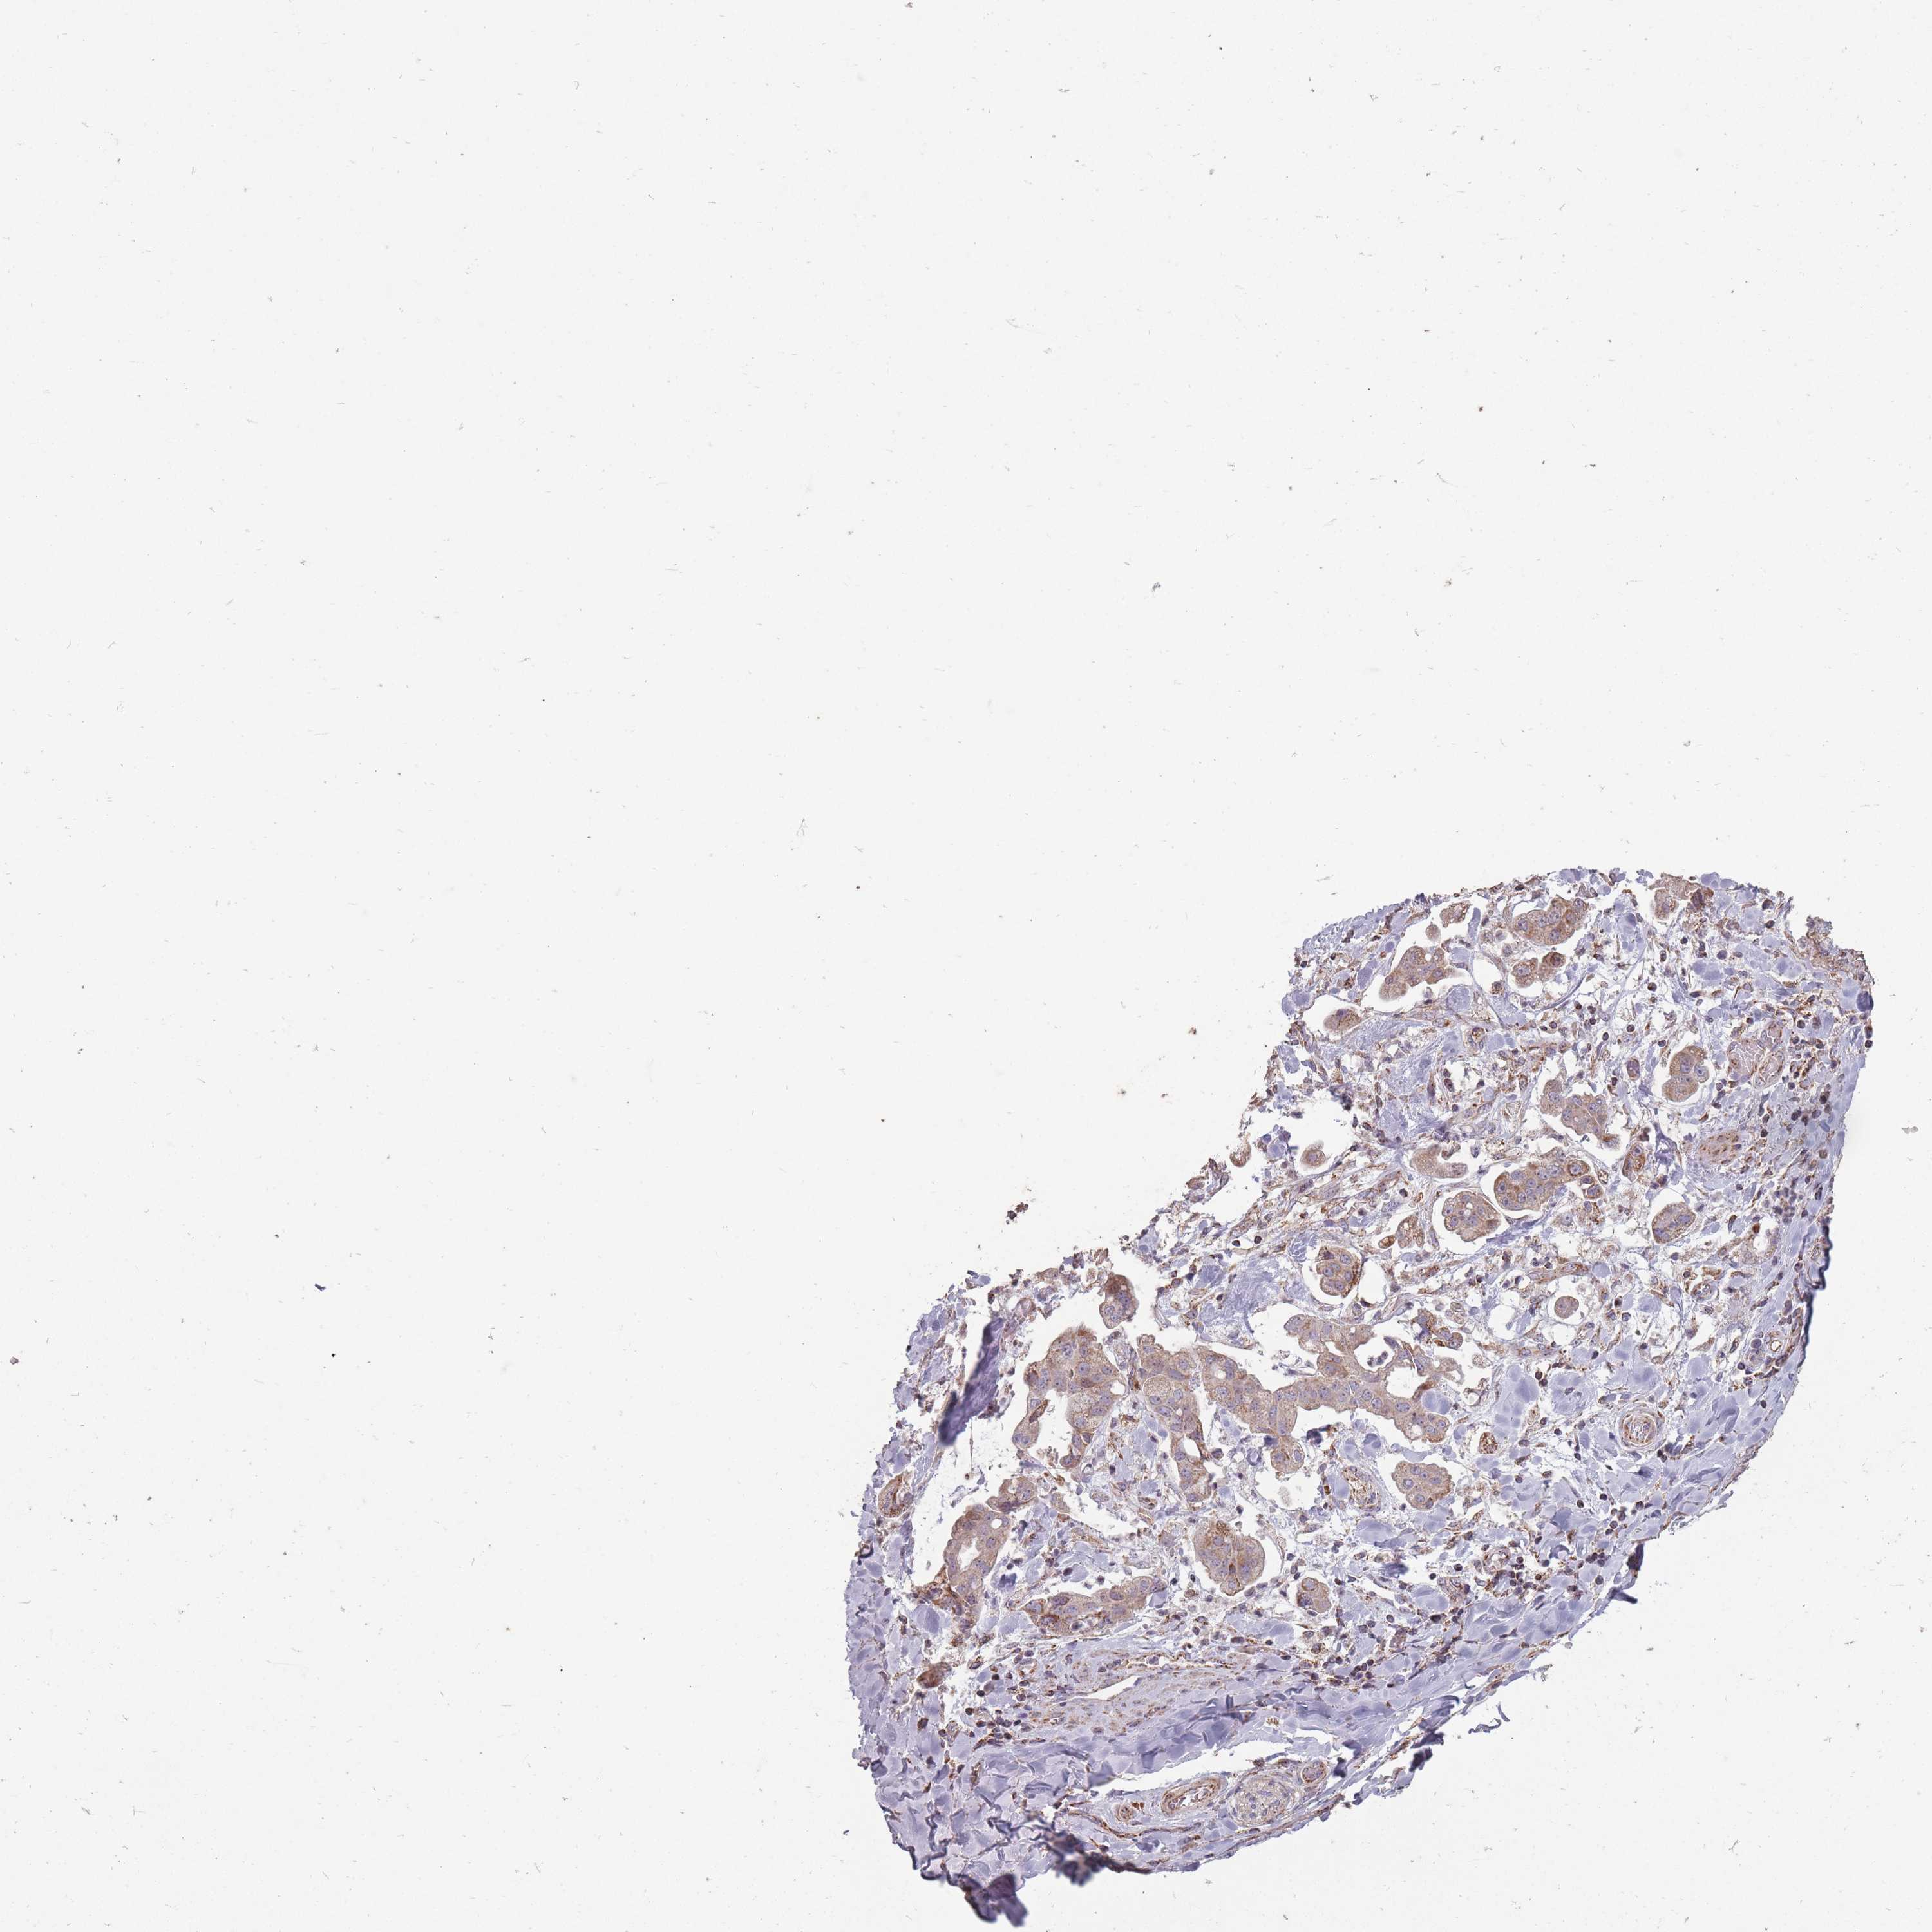

STOMACH CANCER - Protein expressioni

A mouse-over function shows sample information and annotation data. Click on an image to view it in a full screen mode. Samples can be filtered based on level of antibody staining by selecting one or several of the following categories: high, medium, low and not detected. The assay and annotation is described here.

Note that samples used for immunohistochemistry by the Human Protein Atlas do not correspond to samples in the TCGA dataset.

Antibody stainingi

Antibody staining in the annotated cell types in the current human tissue is reported as not detected, low, medium, or high, based on conventional immunohistochemistry profiling in selected tissues. This score is based on the combination of the staining intensity and fraction of stained cells.

Each image is clickable and will lead to virtual microscopy that enables deeper exploration of all samples and also displays staining intensity scores, fraction scores and subcellular localization as well as patient and tissue information for each sample.

Antibody HPA051398

Staining

High

Medium

Low

Not detected

Intensity

Strong

Moderate

Weak

Negative

Quantity

>75%

75%-25%

<25%

None

Location

Nuclear

Cytoplasmic/membranous

Cytoplasmic/membranous,nuclear

Adenocarcinoma, NOS